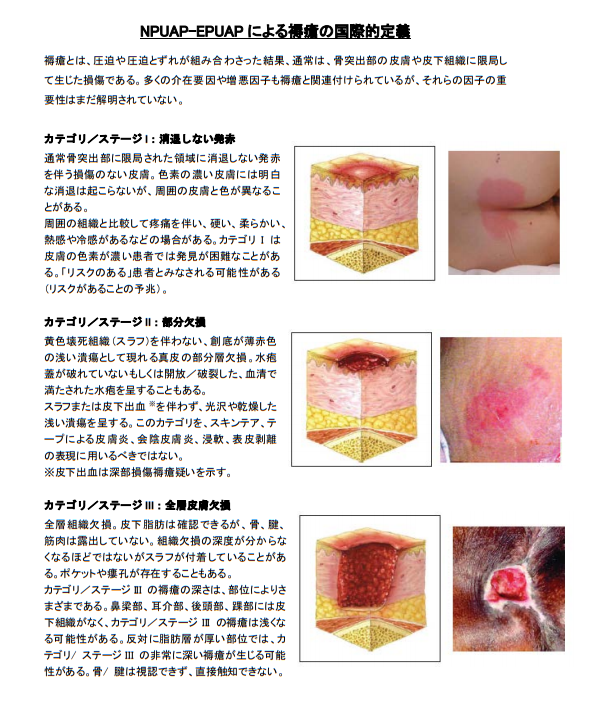

褥瘡の重症度分類を理解しようステージ分類NPUAP、EPUAP分類。

褥瘡治療① 実はあまり知られていない必須の褥瘡知識:褥瘡の治療法は深さによって異なる! -皮膚科専門医が伝授!医療従事者のための高齢者皮膚トラブル対策講座。

医師監修・作成 褥瘡 床ずれ の検査や分類などMEDLEY メドレー。

内科医に役立つ皮膚科の知識 褥瘡臨床雑誌内科 105巻4号医書.jp。

褥瘡治療① 実はあまり知られていない必須の褥瘡知識:褥瘡の治療法は深さによって異なる! -皮膚科専門医が伝授!医療従事者のための高齢者皮膚トラブル対策講座。